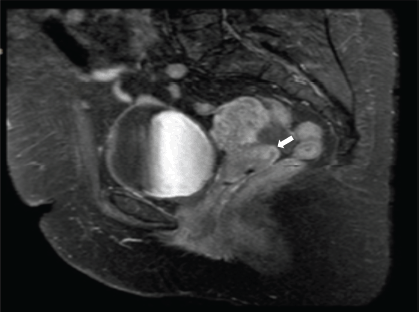

She is subsequently referred to the National Institute of Neoplastic Diseases (22.08.2016) and is seen in the gynecologic oncology service, where she is evaluated. Patient ECOG 1, no peripheral adenopathies. External genitalia preserved, at speculoscopy 2 cm tumour is observed dependent on the posterior lip of the cervix. Digitorectal examination: Parametrium free. Complementary studies with tomography of the thorax, abdomen and pelvis (30.08.2016): Uterus with regular borders and contours. Prominent cervix of 5.3 cm of greater diameter, in the posterior lip, there is a hypocaptive area of contrast in an extension of 2 cm, which could correspond to a lesion. No adenopathies are observed in the iliac chains. No free liquid is observed in the cavity (Figure 1). MRI of the pelvis with contrast (2.9.2016): thickening at the level of the cervix of 2 × 2 cm that shows restriction to diffusion and enhances with the contrast substance. No parametrial involvement (Figure 2).

Figure 2. Contrast MRI of the pelvis. Sagittal view. Thickening of 2 × 2 cm at the level of the uterine cervix, predominance of the posterior lip that shows diffusion restriction and enhances with the contrast substance (→).